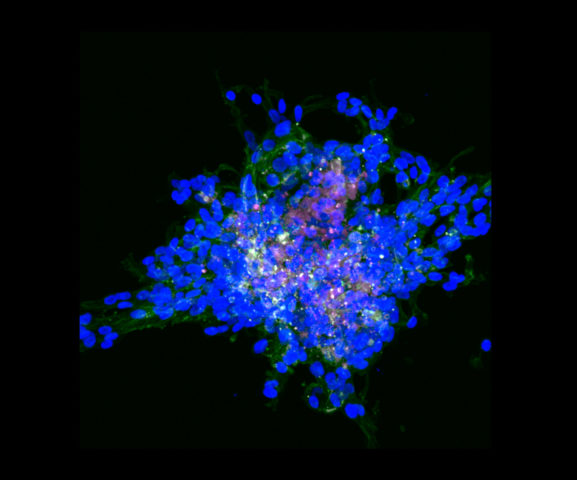

Un primo protocollo approvato a livello internazionale prevede la somministrazione di atezolizumab e nab-paclitaxel per i tumori mammari basal-like (caratteristica istopatologica dei triple negative). L’anticorpo monoclonale atezolizumab agisce come inibitore del checkpoint, specificamente la proteina PD-L1 mentre nab-paclitaxel, dal nome commerciale Abraxane, interferisce con la proprietà delle cellule tumorali di proliferare (quindi interferisce con la divisione delle cellule).